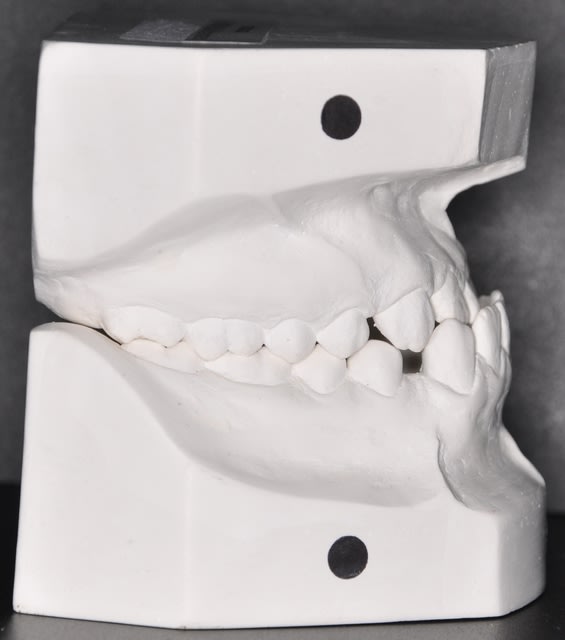

Saïd, je pense que nous devons faire confiance à Takamatika. C'est lui (elle ?) qui a fait l'examen clinique et positionné les modèles en plâtre.

oui mais Takamatika a mis les modèle en PIM et Saïd voudrait les voir en RC. Quel est le chemin de fermeture?

Personnellement dans un cas de lateromandibulie combinee (d'origine fonctionnelle, positionnelle et/ou squelettique) un montage sur articulateur devient indisponsable avec une radio de face afin d'estimer la dissymetrie mandibulaire.